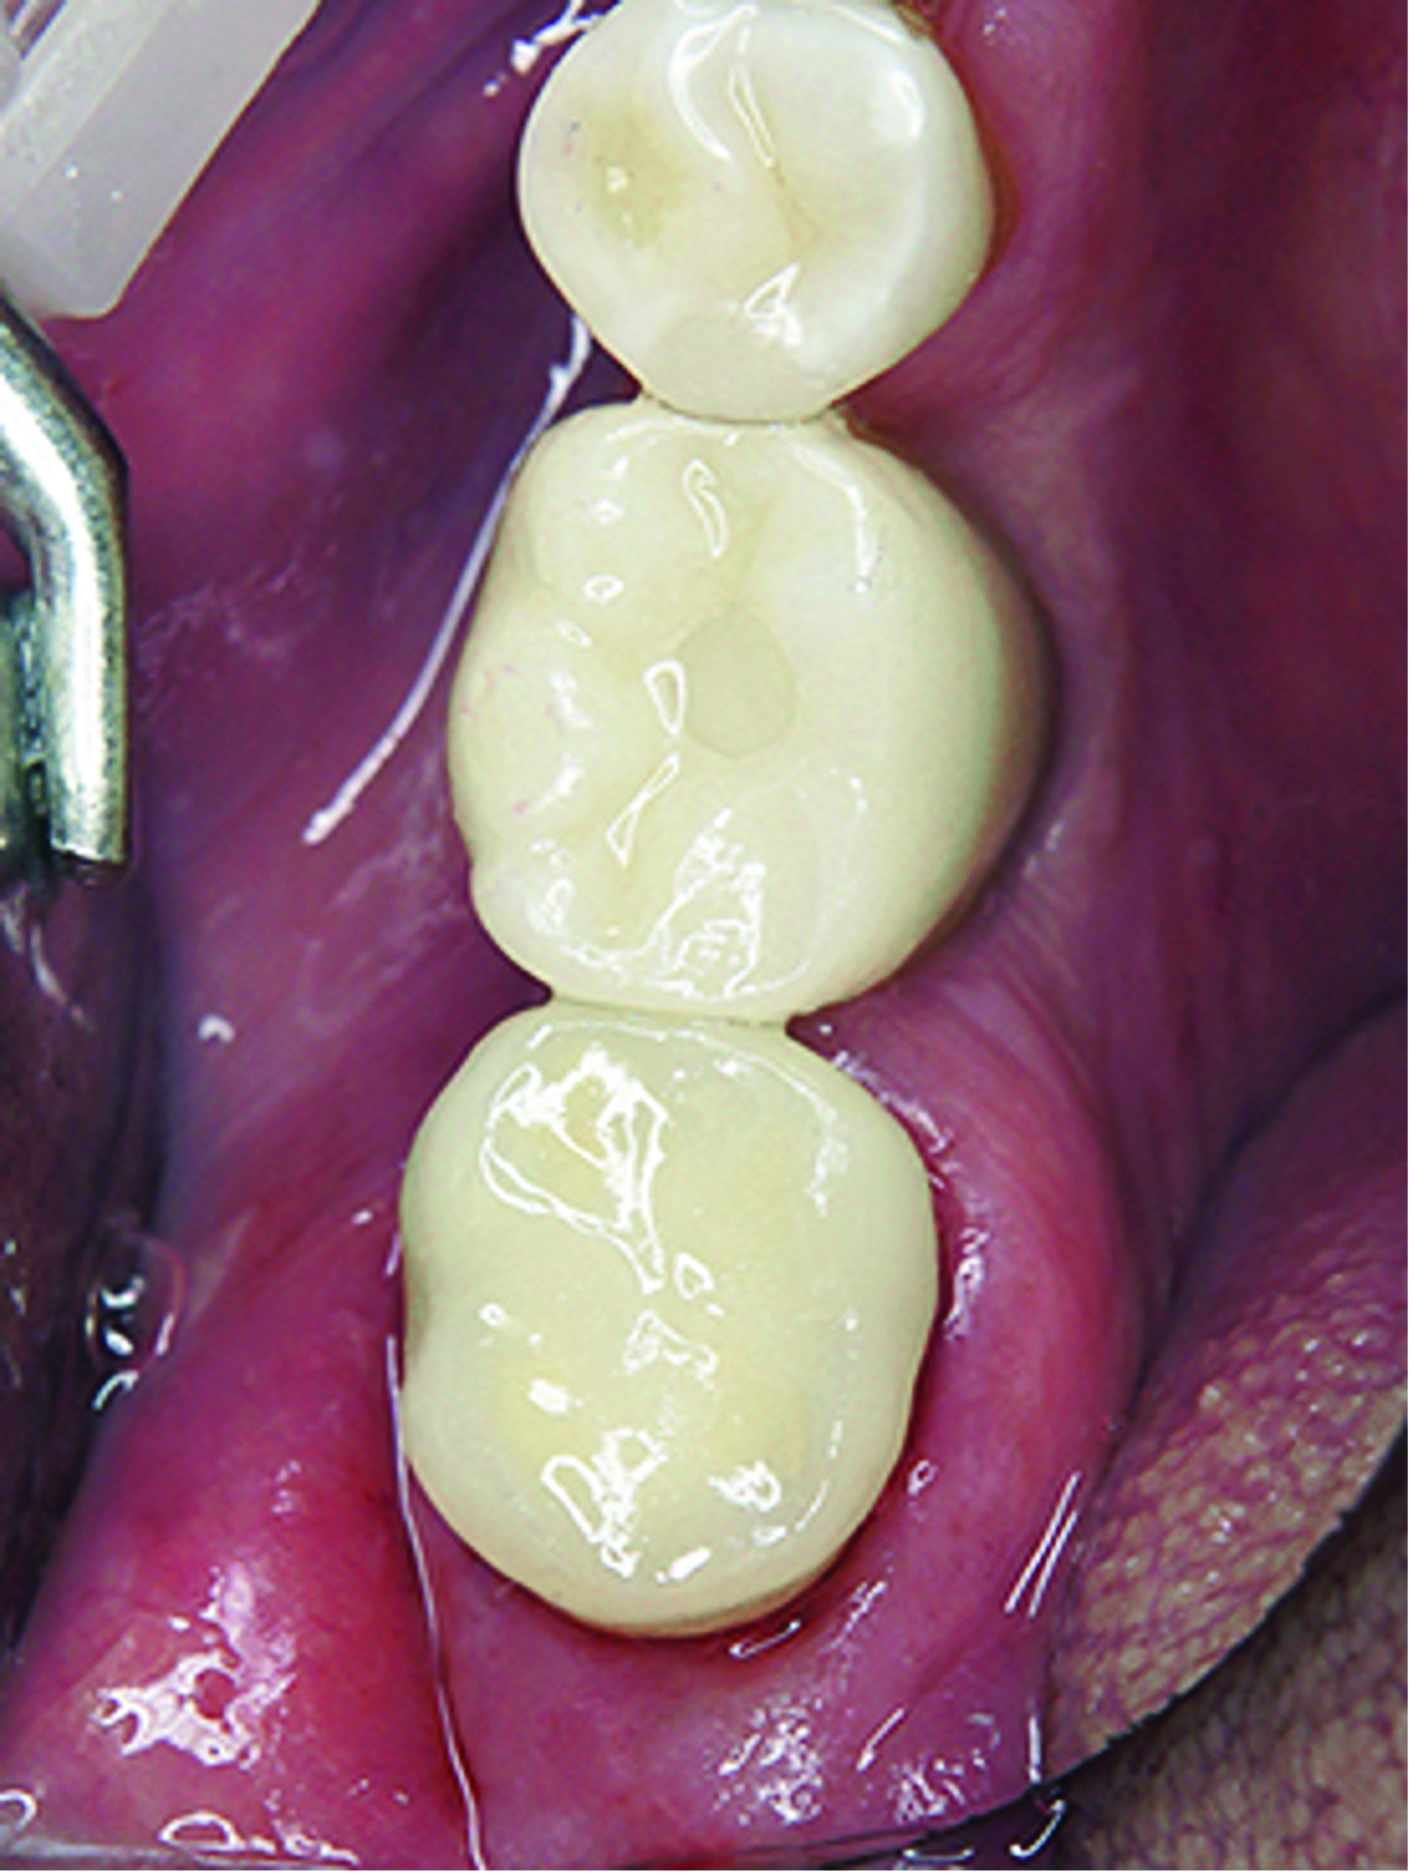

Fig 21. Vestibular view of the treatment result.

Figure 21

Fig 22. Occlusal view of the treatment result.

Figure 22

The final step of the clinical workflow involves complete isolation of the operative site using a rubber dam under the DOM to prevent contamination before cementation. After isolation was achieved the restoration was tried in to verify full seating, thus ensuring a precise marginal fit and tight proximal contacts, with smooth transitions and no overhangs (Figure 16).

The proximal contact was checked by gently passing dental floss through the contact point without it snapping, followed by lateral movement of the teeth to avoid dislodging the restoration. Articulating paper was then used to assess static and dynamic occlusion, with any high spots adjusted microscopically to prevent over-reduction. Microscopic verification of the occlusion helps ensure that the restoration aligns with the patient's bite and functions seamlessly with the natural dentition (Figure 21 and Figure 22).